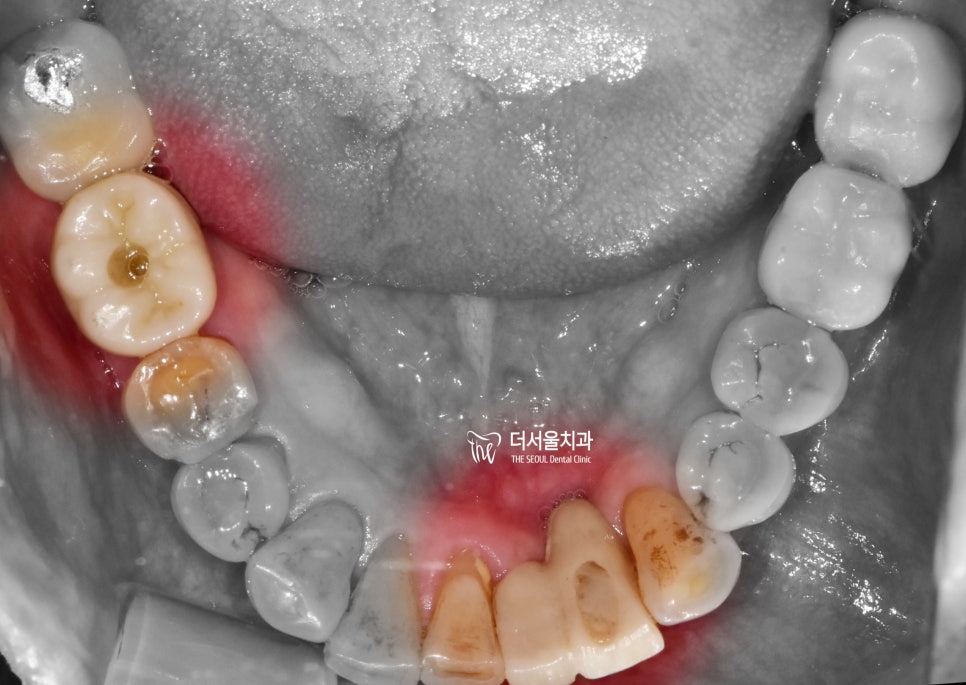

구강 내 사진에서도 이러한 증세는

그대로 보여집니다.

잇몸이 아래로 많이 내려가 있죠?